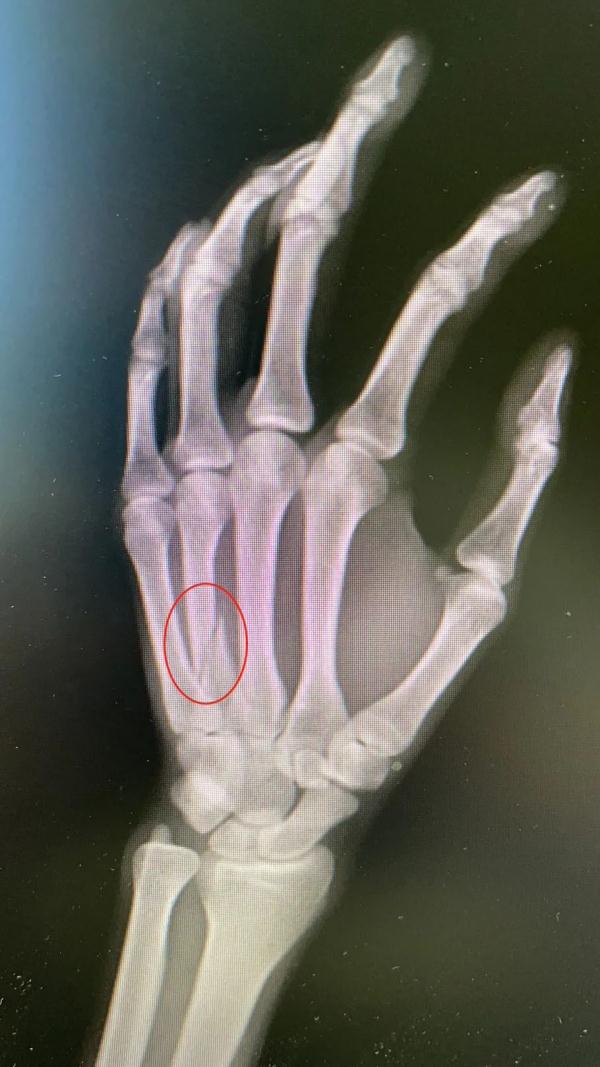

“右手第四掌骨,有明顯的骨折,因為骨部位有旋轉移位,需要手術固定。”在武漢市第四醫院,手外一科醫生陳焱介紹。

陳焱解釋,像這種握拳後撞擊硬物而導致骨折的,在醫學上通常稱為“拳擊手骨折”,拳擊手骨折是一種發生於掌骨的骨折,常發於第4、第5掌骨。

這種骨折很少發生在有拳套保護的職業拳擊手身上。而更多見於街頭打鬥中用“裸拳”打鬥的人群。“許多人認為拳頭很硬,實際上手部掌骨與身體其部位骨皮質相比,屬於最薄的部位,所以當父親周先的拳頭打碰到兒子前臂肘關節時,骨皮質較薄的手掌骨會骨折。”